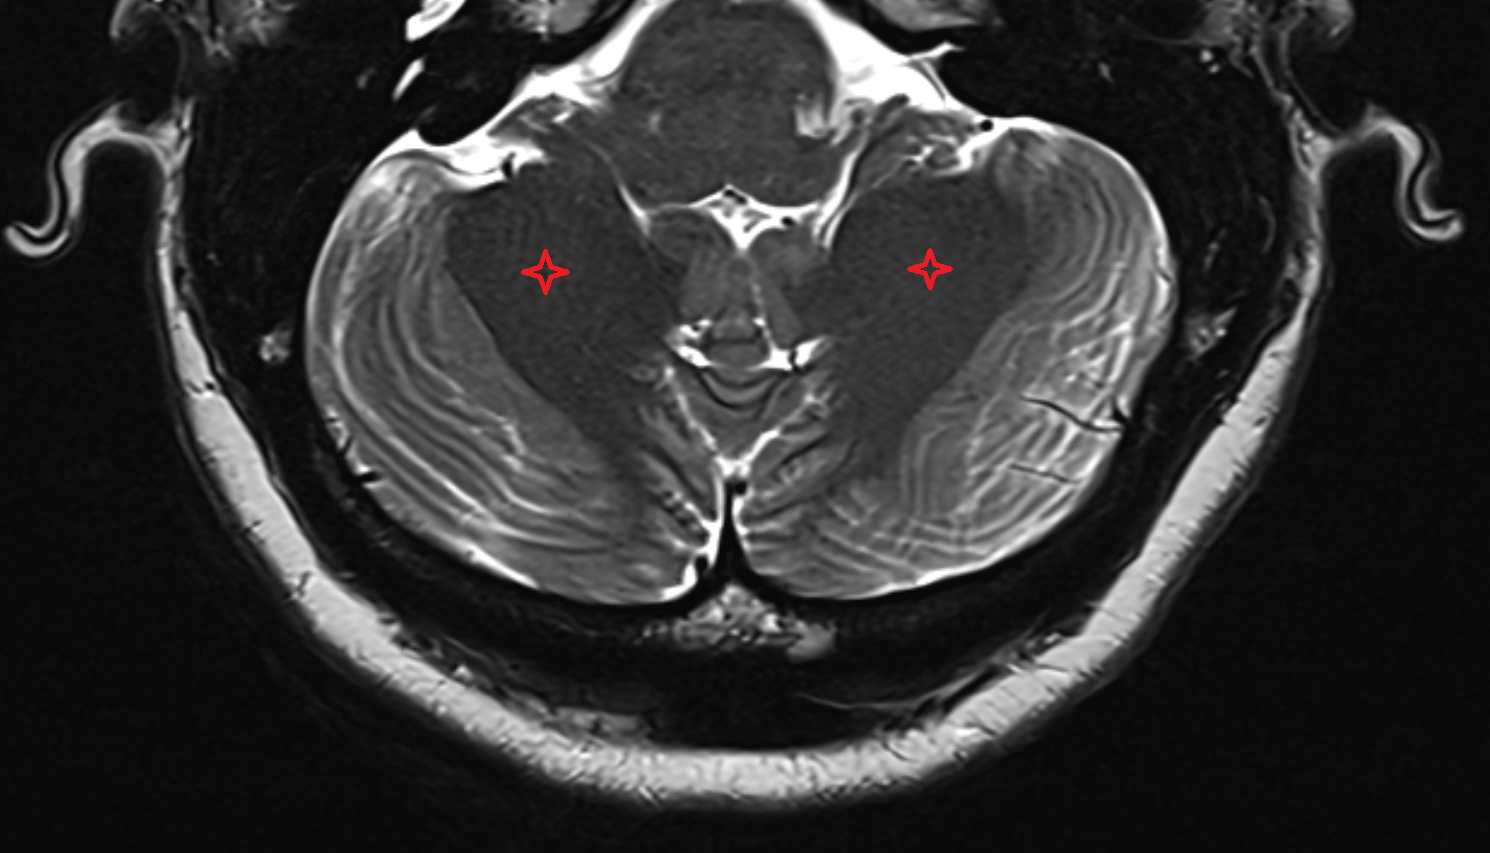

- Cerebellum

- Crus I of ansiform lobule of cerebellum

- Crus II of ansiform lobule of cerebellum

- Paramedian lobule (HVII) of cerebellum

- Simple lobule (HVI) of cerebellum

- Anterior quadrangular lobule (HV) of cerebellum

- Anterior quadrangular lobule (HlV) of cerebellum

- Biventral lobule (HVIII) of cerebellum

- Cerebellar tonsil (H IX)